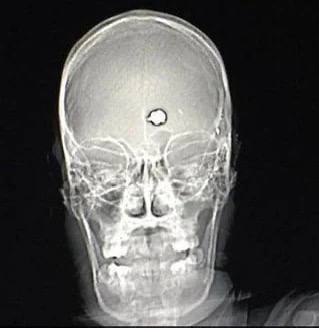

Пациент дурки выстрелил себе в голову из пистолета в попытке покончить с жизнью, но случайно вылечился.

В соцсетях вспоминают реальный случай из 1980-х: американец с тяжёлым обсессивно-компульсивным расстройством (ОКР) выстрелил себе в голову из пистолета калибра .22.

Пуля вошла в левую лобную долю, отвечающую за навязчивые мысли. ОКР исчезло, а интеллект остался, и через несколько лет мужчина даже стал отличником в колледже.